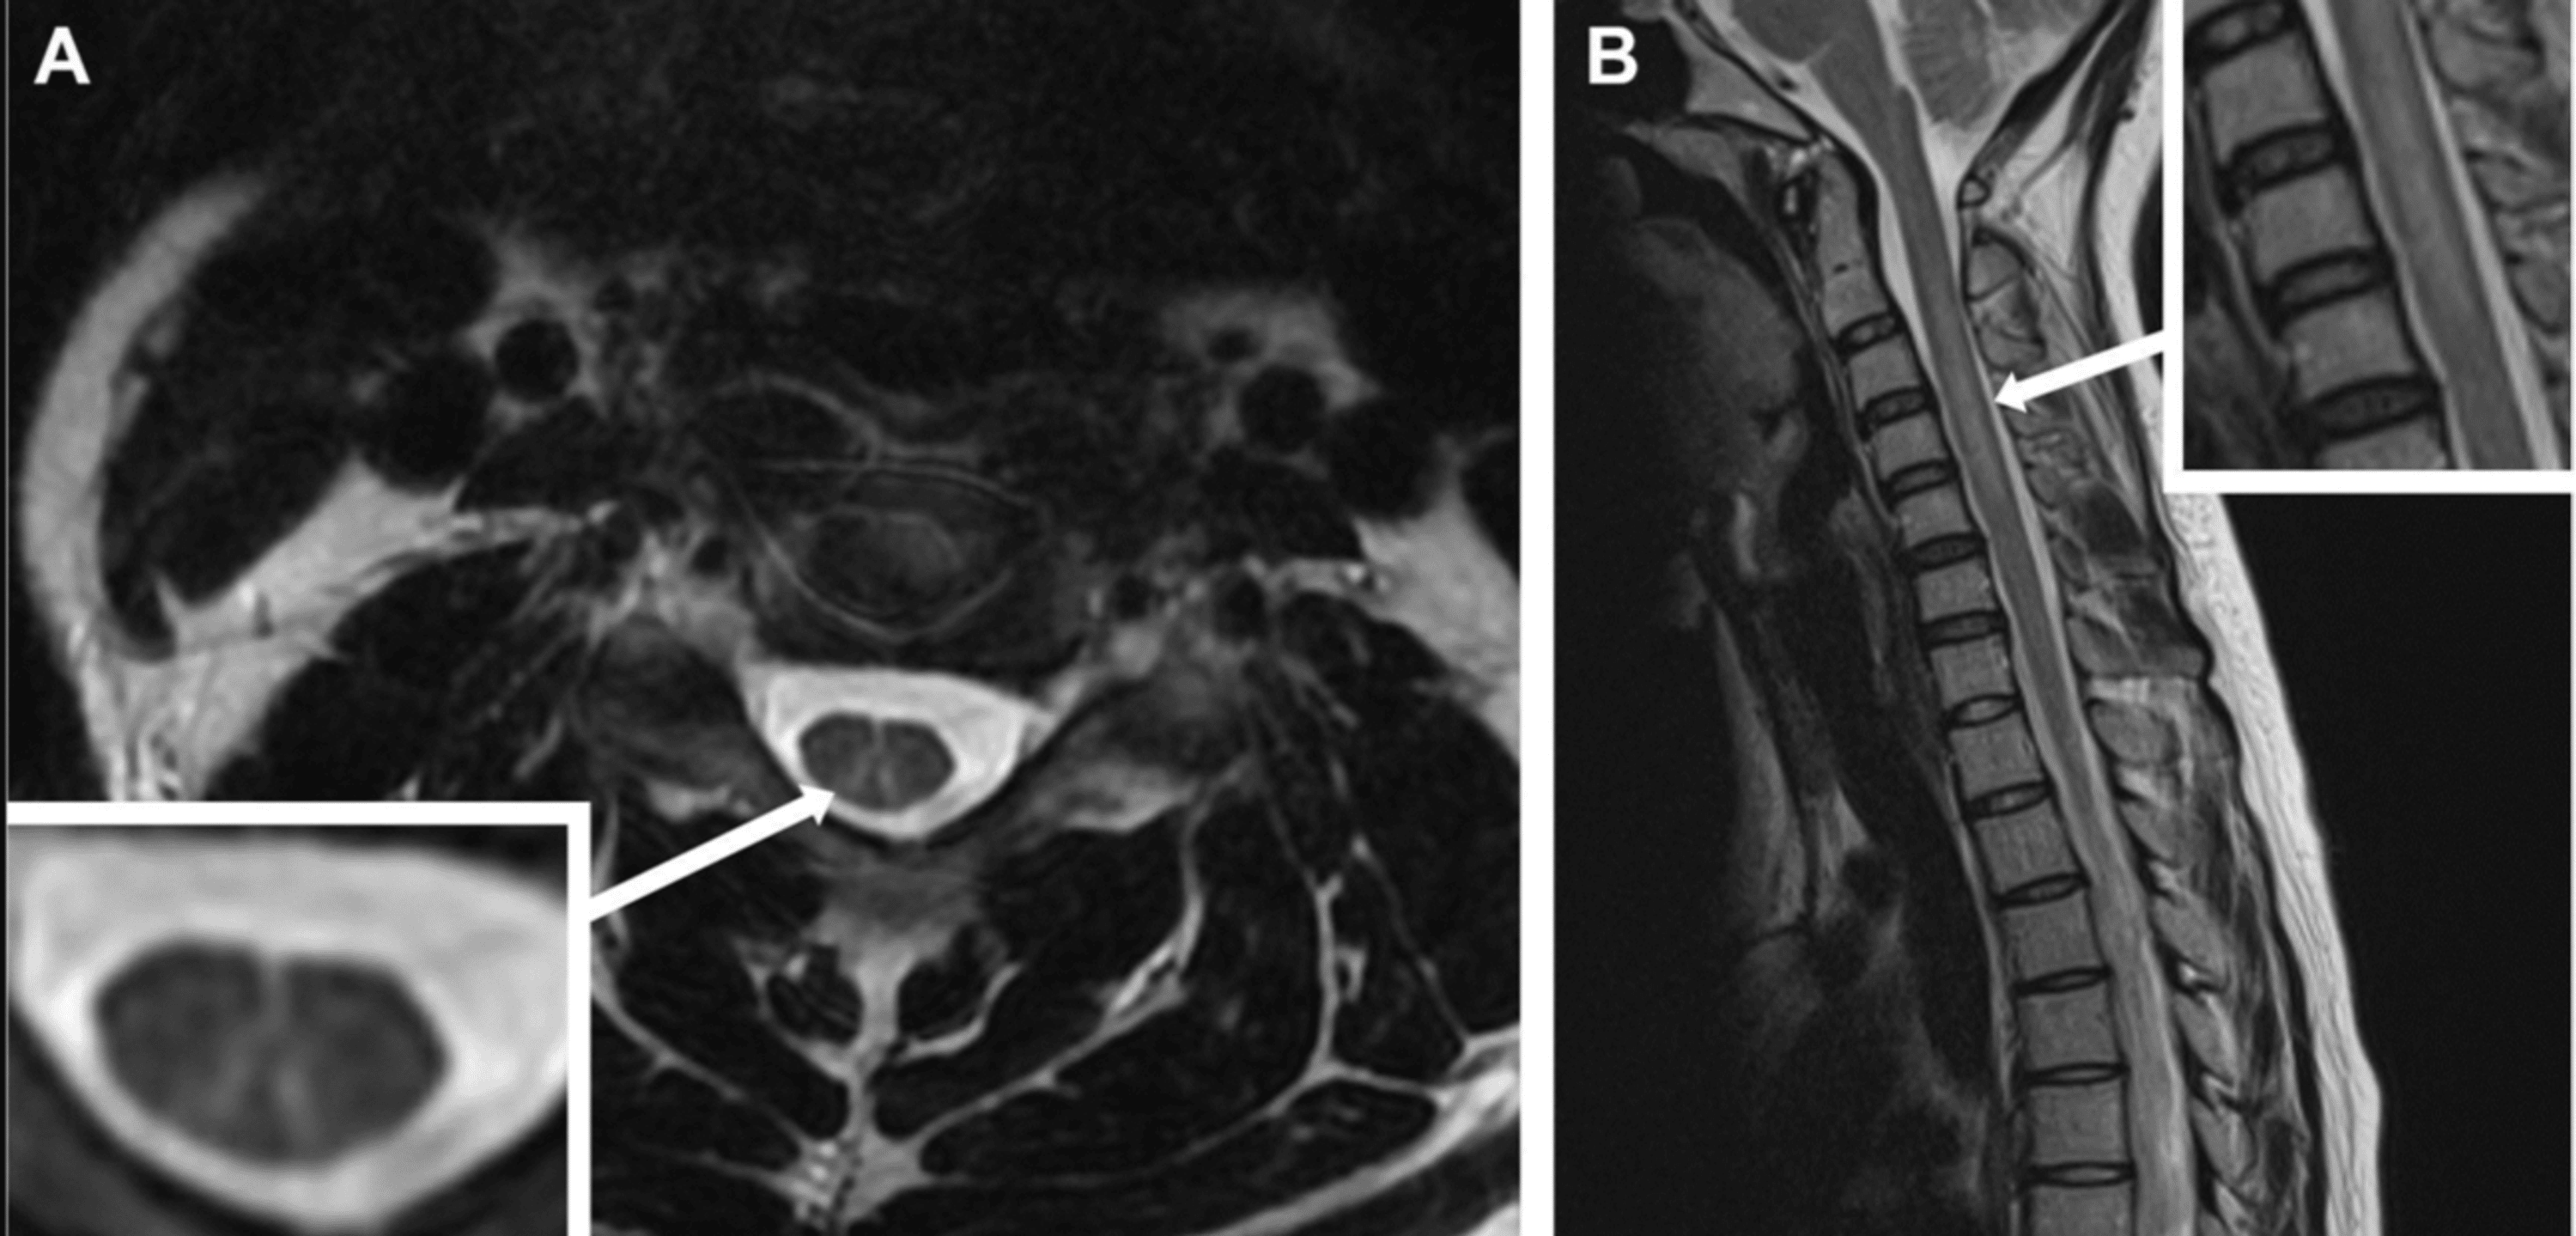

Magnetic resonance imaging (MRI) of the spinal cord typically shows T2 hyperintensities in the dorsal columns, especially in the cervical and upper thoracic regions, consistent with SCD (Figure 2) [8]. Nerve conduction studies may show axonal or demyelinating features.

In addition, haematological changes such as macrocytic anaemia, leukopenia, and thrombocytopenia may occur, although these are less frequent in acute settings [9]. Elevated MMA and homocysteine levels are more reliable markers of functional B12 deficiency than serum B12 itself, and they should be checked when neurological symptoms are suspected [10].